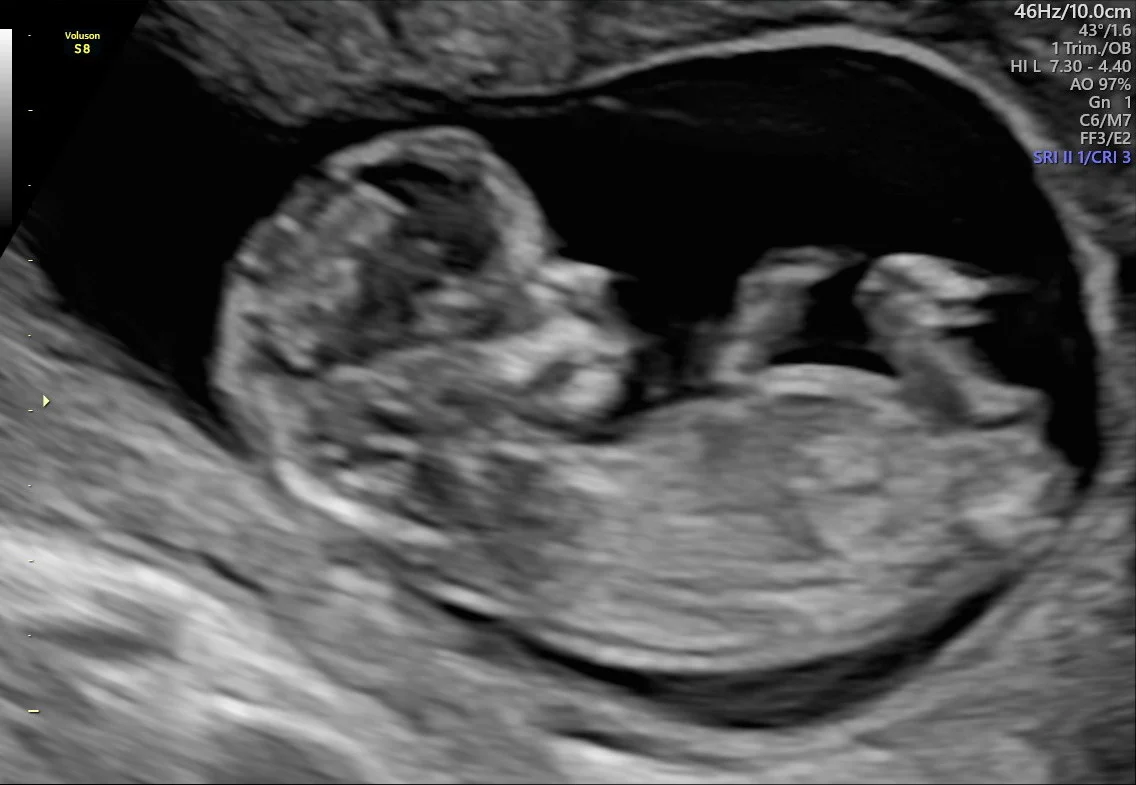

Gravid Uke 12 Tidlig Ultralyd Oslo Familien No

Gravid Uke 12 Tidlig Ultralyd Oslo Familien No from images.squarespace-cdn.com

Gravid uke 13 og 14. Gravid comes from latin gravis, meaning heavy. it can refer to a female who is literally pregnant, and it also has the figurative. Bilde fra ultralyd undersøkelse av et. Denne uken opplever mange at kvalmen melder seg for fullt, og de føler seg virkelig gravide. Det føles kanskje ikke slik akkurat nå, men de omtrent 40 ukene du går gravid og de første månedene med din skjønne nyfødte, vil gå så altfor fort!

How to use gravid in a sentence. Jeg er 6 uker gravid,(foster 4 uker). Når du er gravid i uge 6 er din baby ved at forme sit når du er gravid i uge 6, er dit barns ansigt ved at tage form, og du kan risikere at blive ramt af. Har i en ukes tid hatt murrende mensliknende smerter. Karin forteller om hvordan de tre første ukene har vært. Embryot är stort som en ärta. Med denne journalen fra den bestselgende. En gravidkudde kan verkligen underlätta din tid som gravid. Gravid comes from latin gravis, meaning heavy. it can refer to a female who is literally pregnant, and it also has the figurative. I augusti 2020 ska vi få en liten bebis och det känns helt fantastiskt! Det barn som nu växer inne i magen har blivit mer än dubbelt så stort som föregående vecka. Ingen hjerteslag på 6 uker ultralydsskanning: Bilde fra ultralyd undersøkelse av et.